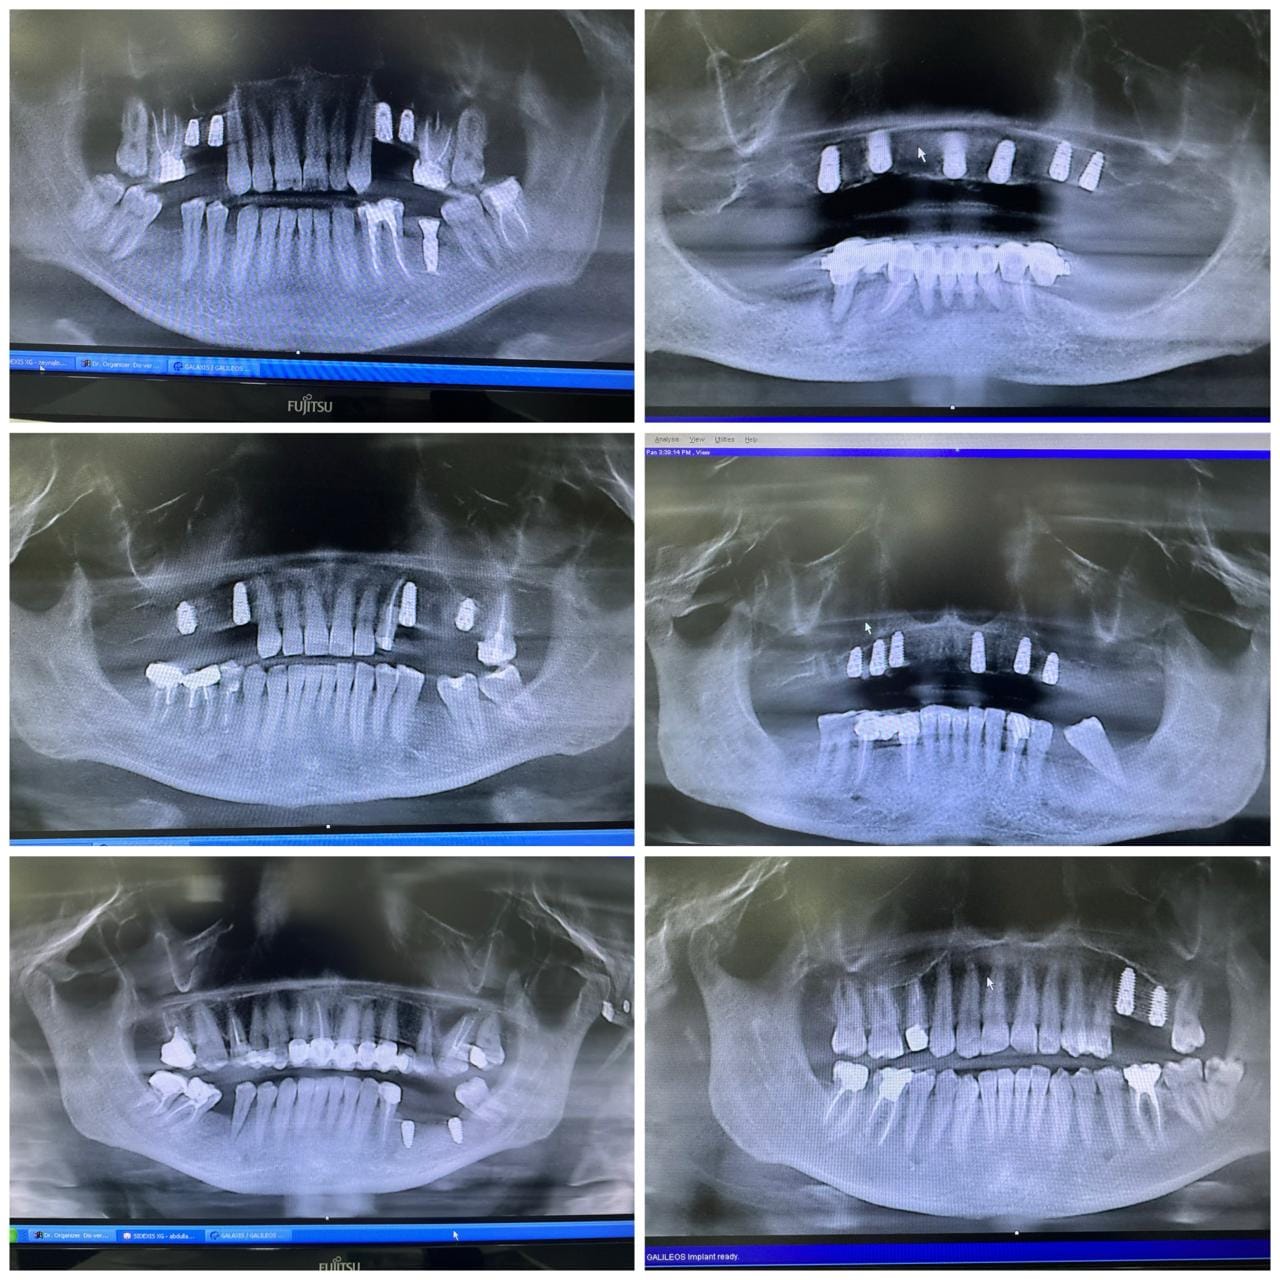

İmplant rentgenləri